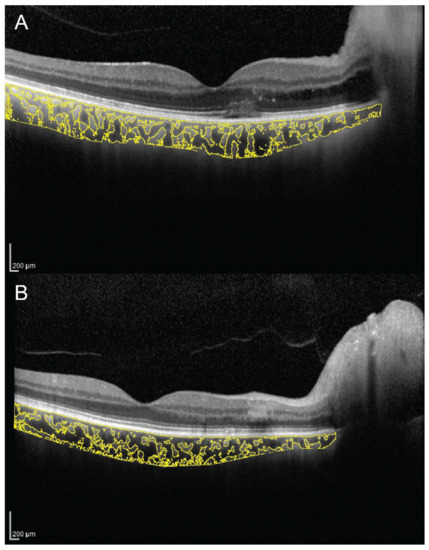

Sonoda et al. firstly described a technique to evaluate subfoveal LCA and SCA by an image binarization process of the EDI spectral domain (SD)-OCT foveal scan using the free software ImageJ (National Institutes of Health, Bethesda, MD, USA) [7,11]. Briefly, the OCT image is opened in ImageJ, and the polygon tool is used to select a region of interest of 1500 µm wide, centered on the fovea. The upper boundary of the region of interest is traced along the choroidal–RPE junction and the lower boundary along the sclerochoroidal junction to identify the total choroidal area (TCA). Image brightness is adjusted on the base of the average value obtained from the LCA of three choroidal vessels selected using the oval selection tool. After conversion to an 8-bit image, Niblack’s autolocal threshold is applied to binarize the image and to demarcate the LCA and the SCA. The image is converted to a red, green and blue image, and the color threshold tool is used to select the dark pixels, representing the LCA. The TCA and LCA are finally measured (Figure 1). The SCA is then obtained by subtracting LCA from TCA. The ratio between LCA and TCA is calculated.

Figure 1. Choroidal vascularity index (CVI) calculation with binarization of enhanced-depth imaging (EDI) spectral domain optical coherence tomography (SD-OCT) image. Choroidal boundaries were traced to identify the total choroidal area (yellow lines) (A). The image was binarized using Niblack’s auto-local threshold (B). The color threshold tool was used to select the dark pixels, representing the luminal area (yellow lines) (C). The CVI is calculated dividing luminal area by total choroidal area.